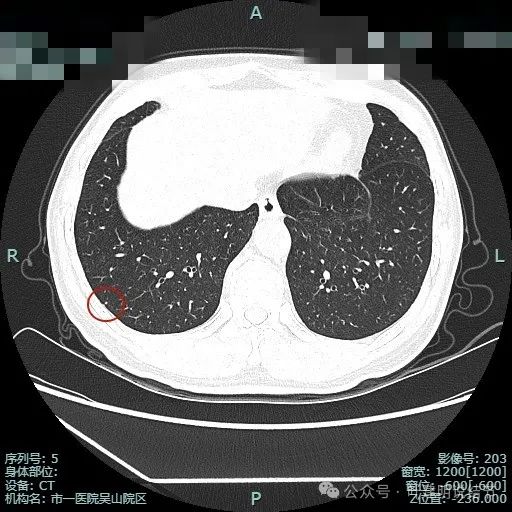

图片

主病灶术前定位,医用胶就在病灶边上(上图绿色的是定位医用胶,红色箭头指的是病灶6)。